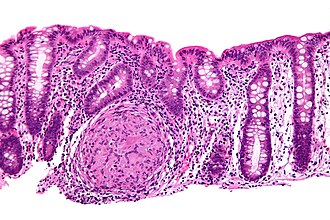

Crohn's disease. H&E stain. | |

Crohn's disease, abbreviated as CD, is a type of inflammatory bowel disease. It is the bread and butter of gastroenterology, and is often seen by pathologists.